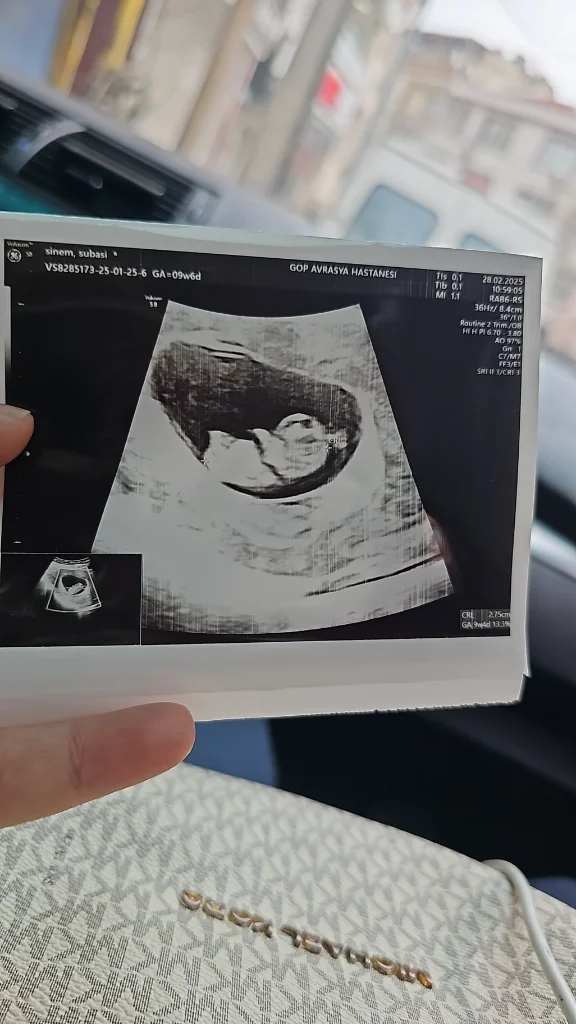

S sinemozay Yeni Üye Kayıtlı Üye 20 Şubat 2025 9 0 1 32 1 Mart 2025 Konu Sahibi Konu Sahibi xnadia99 #72 Tahminlerinizi alabilir miyim kızlar Eklentiler 1000032006.webp 66,1 KB · Görüntüleme: 27